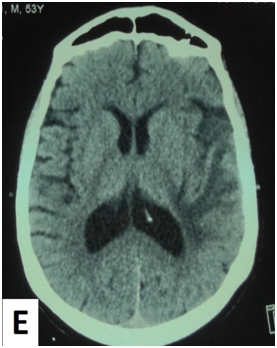

The cerebral MRI showed heterogeneous decreased signal intensity in T1, T2 and Flair-weighted images with variable sizes, surrounded by large area of increased signal intensity in T2 and Flair weighted-images with mass effect on the ipsilateral ventricle (Figure 1). The T1 sequences with intravenous gado injection showed heterogeneous gado enhancement corresponding to the area withT2 and Flair decreased signal intensity (Figure 2). This pattern corresponds to the “swiss cheese” and “soap bubble” aspect. The diffusion weited image showed increased ADC with increased water mobility in left temporal lobe (Figure 3). The radiological conclusion was temporal radionecrosis with large vasogenic edema, or the differential diagnosis of cerebral metastasis of the primary nasopharyngeal carcinoma. Thus, a spectroscopy was performed, and showed decreased peak of N-Acetyl-Aspartate (NAA) and Creatinine (Cr), with normal choline peak. The diagnosis of temporal radio necrosis was established. The patient was proposed to hyperbaric oxygen. His Oto-rhino-laryngeal examination was normal, as much s the chest X-ray. So a daily 45 minutes session, were performed for 10 successive days, associated to bolus of methylprednisolone (240mg/d for 10 days), anti-platelet agent (aspirin 160mg/d). The evolution was favorable, with regression of vestibular signs, improvement of memory and phasic troubles with recovering four lost points in MoCA score. The cerebral CT scan showed partial regression of the gliosis with no more mass effect on the ipsilateral ventricle (Figure 4).